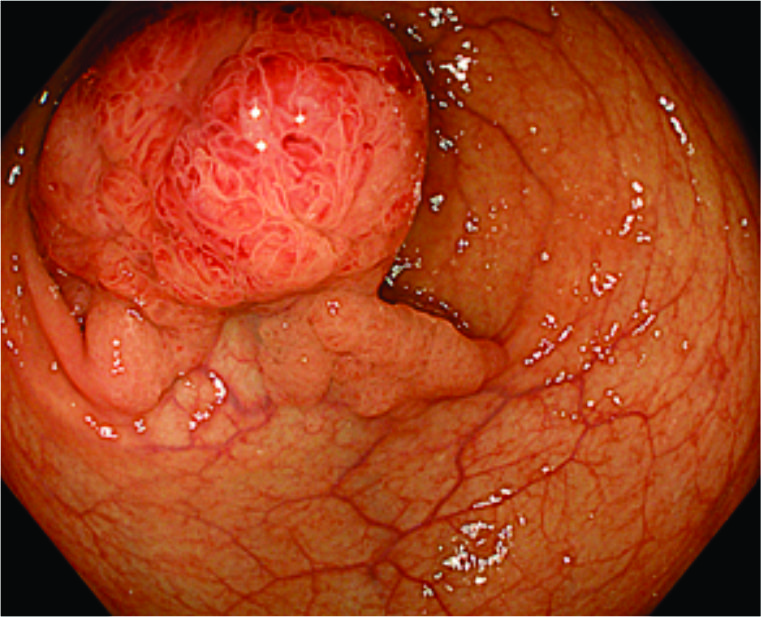

Pictures of large colon polyps, its endoscopic removal and the resection specimen

Endoscopic Removal

Endoscopic submucosal dissection

• For polyps that are too large for EMR or for early cancerous lesions, the doctor uses a more advanced and time-consuming technique called ESD.

• In ESD, a dye-mixed solution is injected into the deeper tissue layer (submucosa) to lift the polyp or lesion.

• The doctor then uses an electrosurgical knife to cut and remove the polyp or lesion in one piece for a complete pathological assessment.